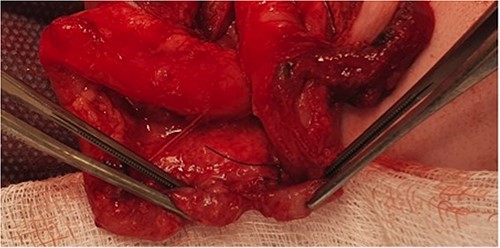

He presented at 6 weeks of age with circulatory shock requiring inotropic support and a short history of sudden abdominal distension and non bilious vomiting. He had been having regular episodes of SVT, all self limiting. Laparotomy demonstrated malrotation and a 540°midgut volvulus with extensive bowel necrosis. A fulcrum of ileum was densely adherent to the descending colon. Following intestinal resection he was left with 40 cm of small bowel from the duodenojejunal flexure, 2 cm of distal ileum and an intact colon. Following recovery from this acute episode he was managed for intestinal failure. A contrast enema was performed 10 days later in advance of stoma closure to examine the area of descending colon to which the ileum had been adherent at laparotomy. This demonstrated failure of passage of contrast proximal to the mid descending colon consistent with acquired colonic atresia (Fig. 1). Due to ongoing high stoma output and inability to progress enteral feeds, the infant proceeded to laparotomy, closure of jejunostomy, resection of colonic atresia, and anastomosis at 3 months of age. Macroscopic evidence of the atresia was encountered (Fig. 2). Histology reported a narrow calibre colon to either side of the atresia with fibrotic submucosa, focal fibrovascular proliferation, and clusters of giant cells. He subsequently achieved enteral autonomy.

Intra-operative photograph of acquired colonic atresia in descending colon consistent with radiological findings in Fig. 1.